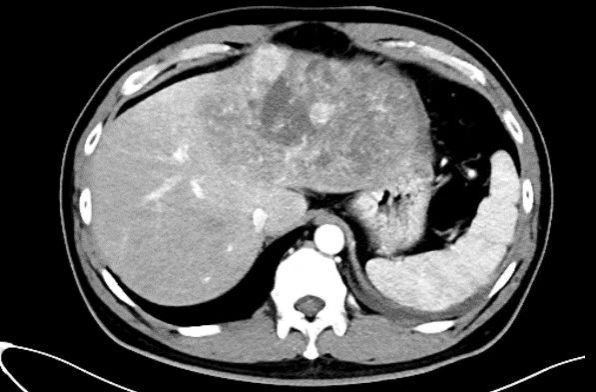

一名四十岁男性患者突发腹痛1天由外院转来。患者有慢性乙肝病史,已经多年未做检查,急诊CT显示:一个直径约16cm×10cm的巨大肝癌充满患者左半肝,挤压侵犯第二肝门肝中静脉(图1,图2)。更危急的是,肿瘤周围大量积液,怀疑肝癌已发生破裂,患者血压90/60mmHg,生命体征岌岌可危。蒋安主任医师接诊后联系输血科董艳迎主任快速输血,迅速纠正休克,使生命体征稳定。